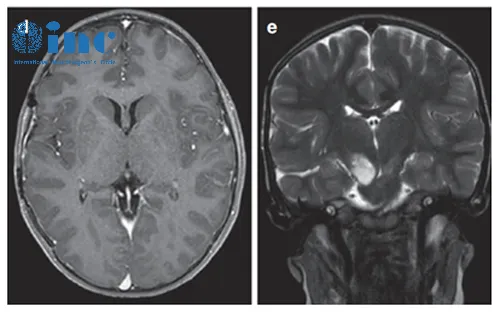

患者情况:3岁患儿因呕吐和巨脑畸形就医。CT及MRI显示右侧丘脑病变伴钙化及后三脑室梗阻,引起脑积水。

在8岁、11岁和13岁时,James T.Rutka教授成功地利用第三脑室内窥镜切开术治疗脑积水,且影像显示肿瘤增大和多发肿瘤囊肿(箭头状),并逐渐出现左上肢震颤。

患儿在13岁时进行了神经导航和超声引导下的活检,证实为脑瘤为WHO I级,毛细胞星形细胞瘤。肿瘤囊肿持续扩大,患儿发展为急性偏瘫。

术后MRI显示囊性占位接触,脑室慢慢恢复正常。四个月后,由于患儿的偏瘫没有改善,Rutka教授为其行经胼胝体半球间入路及肿瘤次全切除术。这一次手术后,患儿偏瘫改善,生长和智力发育正常,近期随访显示脑瘤未复发。免疫组化检测RAFV600E突变免疫无阳性,H3K27M阴性。

术后MR显示肿瘤次全切除,无复发